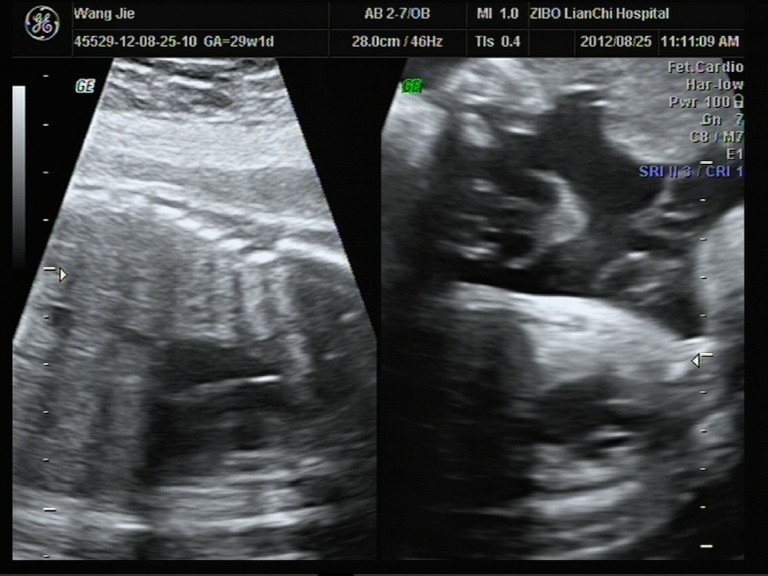

患者信息:女 29岁 病情描述(发病时间、主要症状等):彩超数据和相关照片,想知道宝宝男女。其余大部分照片在我百度空间的相册中。想得到怎样的帮助:想知道宝宝性别。曾经治疗情况及是否有过敏、遗传病史:四维彩超不清楚发哪张好。其余在我的百度空间中。

你好`` 彩超医生是不会把屁股的图像打出来的``` 可以用传统的方法辨别``` 肚子上妊娠纹多`` 一般是男孩`` 肚子不花的`` 一般是女孩``` 如果怀的是男孩`` 妈妈在怀孕期会变丑``` 皮肤变差``` 是女儿妈妈就没多大的变化`` 皮肤会比以前好一点``` 其实这种方法挺准的``你可以参考...一下